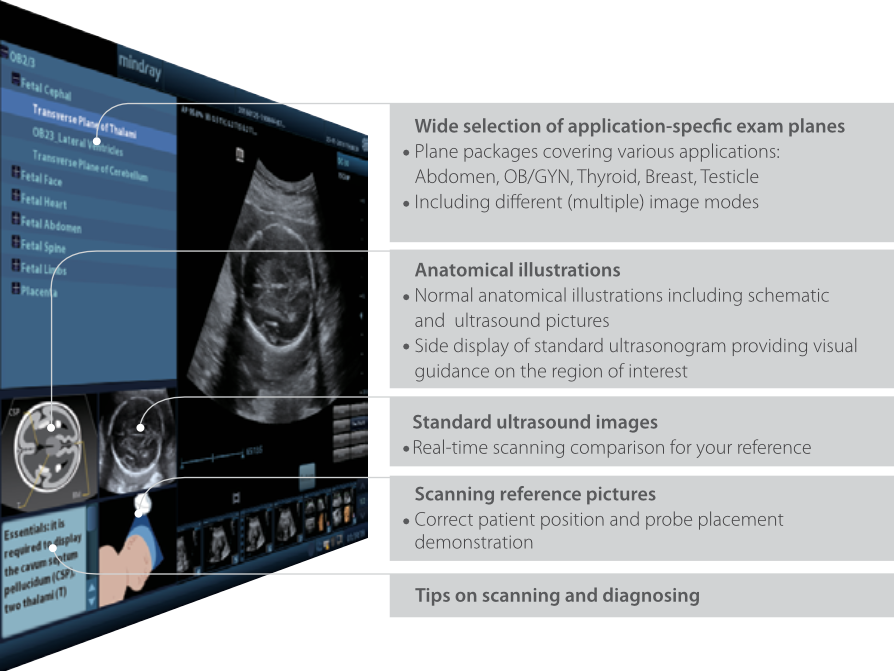

iScanHelper

Strumento didattico integrato dedicato, offre agli utenti una guida informativa sulla scansione ecografica. iScanHelper include illustrazioni anatomiche, immagini ecografiche standard, scansioni di riferimento e consigli su come ottenere una scansione perfetta.